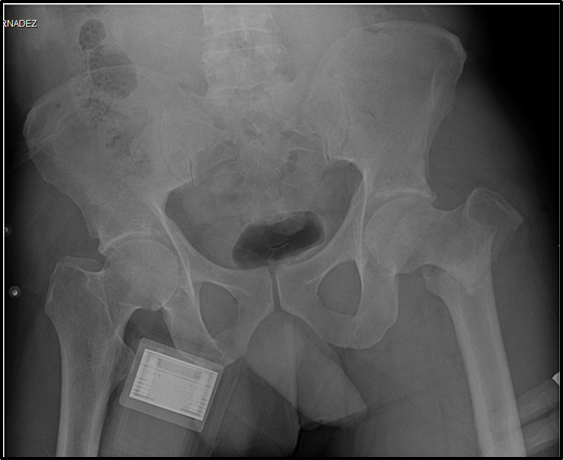

This is a 41-year-old male patient, provided his written informed consent, from and resident of Minatitlán, Veracruz with a history of apparent good health, who was transferred by Red Cross paramedics on July 05, 2019 to the Emergency Department, after suffering a fall from a height of 4 meters in his work area. The diagnosis of polyconcussion was established and the evaluation of cabinet studies identified: distal metaphyseal fracture of the right radius and ulna, intertroncantal fracture of the left femur and costal fractures from the second to the seventh right costal arch; at this time, he was diagnosed as polytrauma/unstable thorax (Figure 1–3).

Figure 2 Rx of Pelvis AP. Intertrochanteric fracture of the left femur is observed.